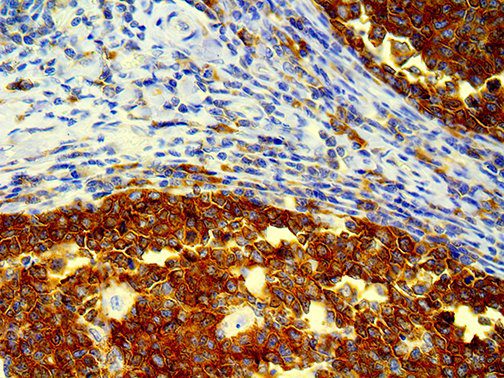

The first cytokines released are interleukin 1β (IL-1β) and tumor necrosis factor-α (TNF-α), which attract a variety of circulating white blood cells (WBCs) to the infection site, including neutrophils, monocytes, macrophages, and natural killer (NK) cells. This response, along with the antipathogenic chemicals released by these cells (i.e., complement), comprise the innate immune response. These cells directly attack the invading pathogen and also release additional cytokines, chief among them interleukin-1 and 6 (IL-6). IL-6 is essential for invoking the adaptive immune response, which calls T-cells, B-cells, and T helper (Th) cells to the infection site. IL-6 also stimulates further recruitment, proliferation and activation of macrophages.

This activation induces inflammatory monocytes to highly express IL-6, starting a localized and then systemic cascade effect that results in hyperproduction of IL-6, which accelerates the inflammatory process. Because IL-6 also increases vascular permeability, excessive levels cause blood vessels to become very leaky. This, along with clotting factors released from vascular endothelial cells, stimulates the coagulation cascade, resulting in microthrombosis (tiny clots), which leads to ischemia and tissue death of the kidney, intestines, heart, liver, brain and extremities.